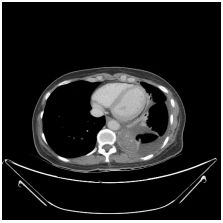

3. This 72-year-old diabetic man was taken to ER for productive cough for 10 days, and rapid progressive dyspnea for 2 days. He also had fever and chill for a week.